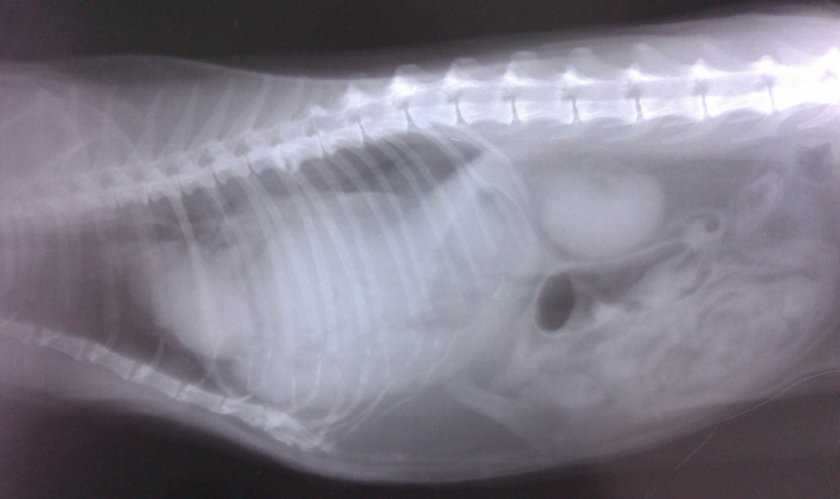

Выпячивание в промежности у собак и кошек, новообразования, локализующиеся в полости таза, могут выступать в брюшную полость или не выходить за пределы полости таза, поэтому для оценки распространения опухоли большое значение имеет рентгенографическое исследование этой области.

Рентгенографическое исследование каудальной части брюшной полости: выявлена выпячивающаяся в область промежности киста предстательной железы с минерализацией стенок фибросаркомы.

по наличию в области паха двусторонней или односторонней припухлости — шарообразной или вытянутой формы визуально, пальпаторно можно установить место выхождение (грыжевые ворота), ущемление или вправимость грыжи. При этом размер может быть разный в зависимости от содержимого. Если грыжевой мешок содержит мочевой пузырь, то при надавливании на него будет мочеиспускание и при этом припухлость уменьшится. Также в грыжевой мешок может выпасть сальник, петли кишечника или матка. Если через грыжевые ворота выпадает беременная матка, то по мере роста плода припухлость увеличивается. Более достоверный метод определения содержимого грыжи УЗИ диагностика. На рентгене тоже можно увидеть изменения в расположении внутренних органов.

Паховую грыжу у собак диагностируют по наличию в области паха двусторонней или односторонней припухлости — шарообразной или вытянутой формы визуально, пальпаторно можно установить место выхождение (грыжевые ворота), ущемление или вправимость грыжи. При этом размер может быть разный в зависимости от содержимого. Если грыжевой мешок содержит мочевой пузырь, то при надавливании на него будет мочеиспускание и при этом припухлость уменьшится. Также в грыжевой мешок может выпасть сальник, петли кишечника или матка. Если через грыжевые ворота выпадает беременная матка, то по мере роста плода припухлость увеличивается. Более достоверный метод определения содержимого грыжи УЗИ диагностика. На рентгене тоже можно увидеть изменения в расположении внутренних органов.